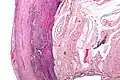

Pathology

Even for clinically certain appendicitis, routine histopathology examination of appendectomy specimens is of value for identifying unsuspected pathologies requiring further postoperative management.[69] Notably, appendix cancer is found incidentally in about 1% of appendectomy specimens.[70]

Pathology diagnosis of appendicitis can be made by detecting a neutrophilic infiltrate of the muscularis propria.

Periappendicitis (inflammation of tissues around the appendix) is often found in conjunction with other abdominal pathology.[71]

Micrograph of appendicitis and periappendicitis. H&E stain

Micrograph of appendicitis showing neutrophils in the muscularis propria. H&E stain

Acute suppurative appendicitis with perforation (at right). H&E stain